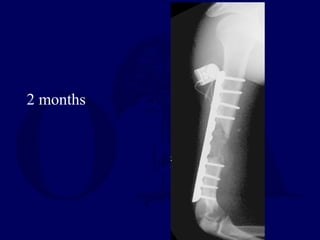

2 months

ORIF with bladeplate

fibular strut allograft

cancellous autograft

CaSO4 pellets

Bone stimulator